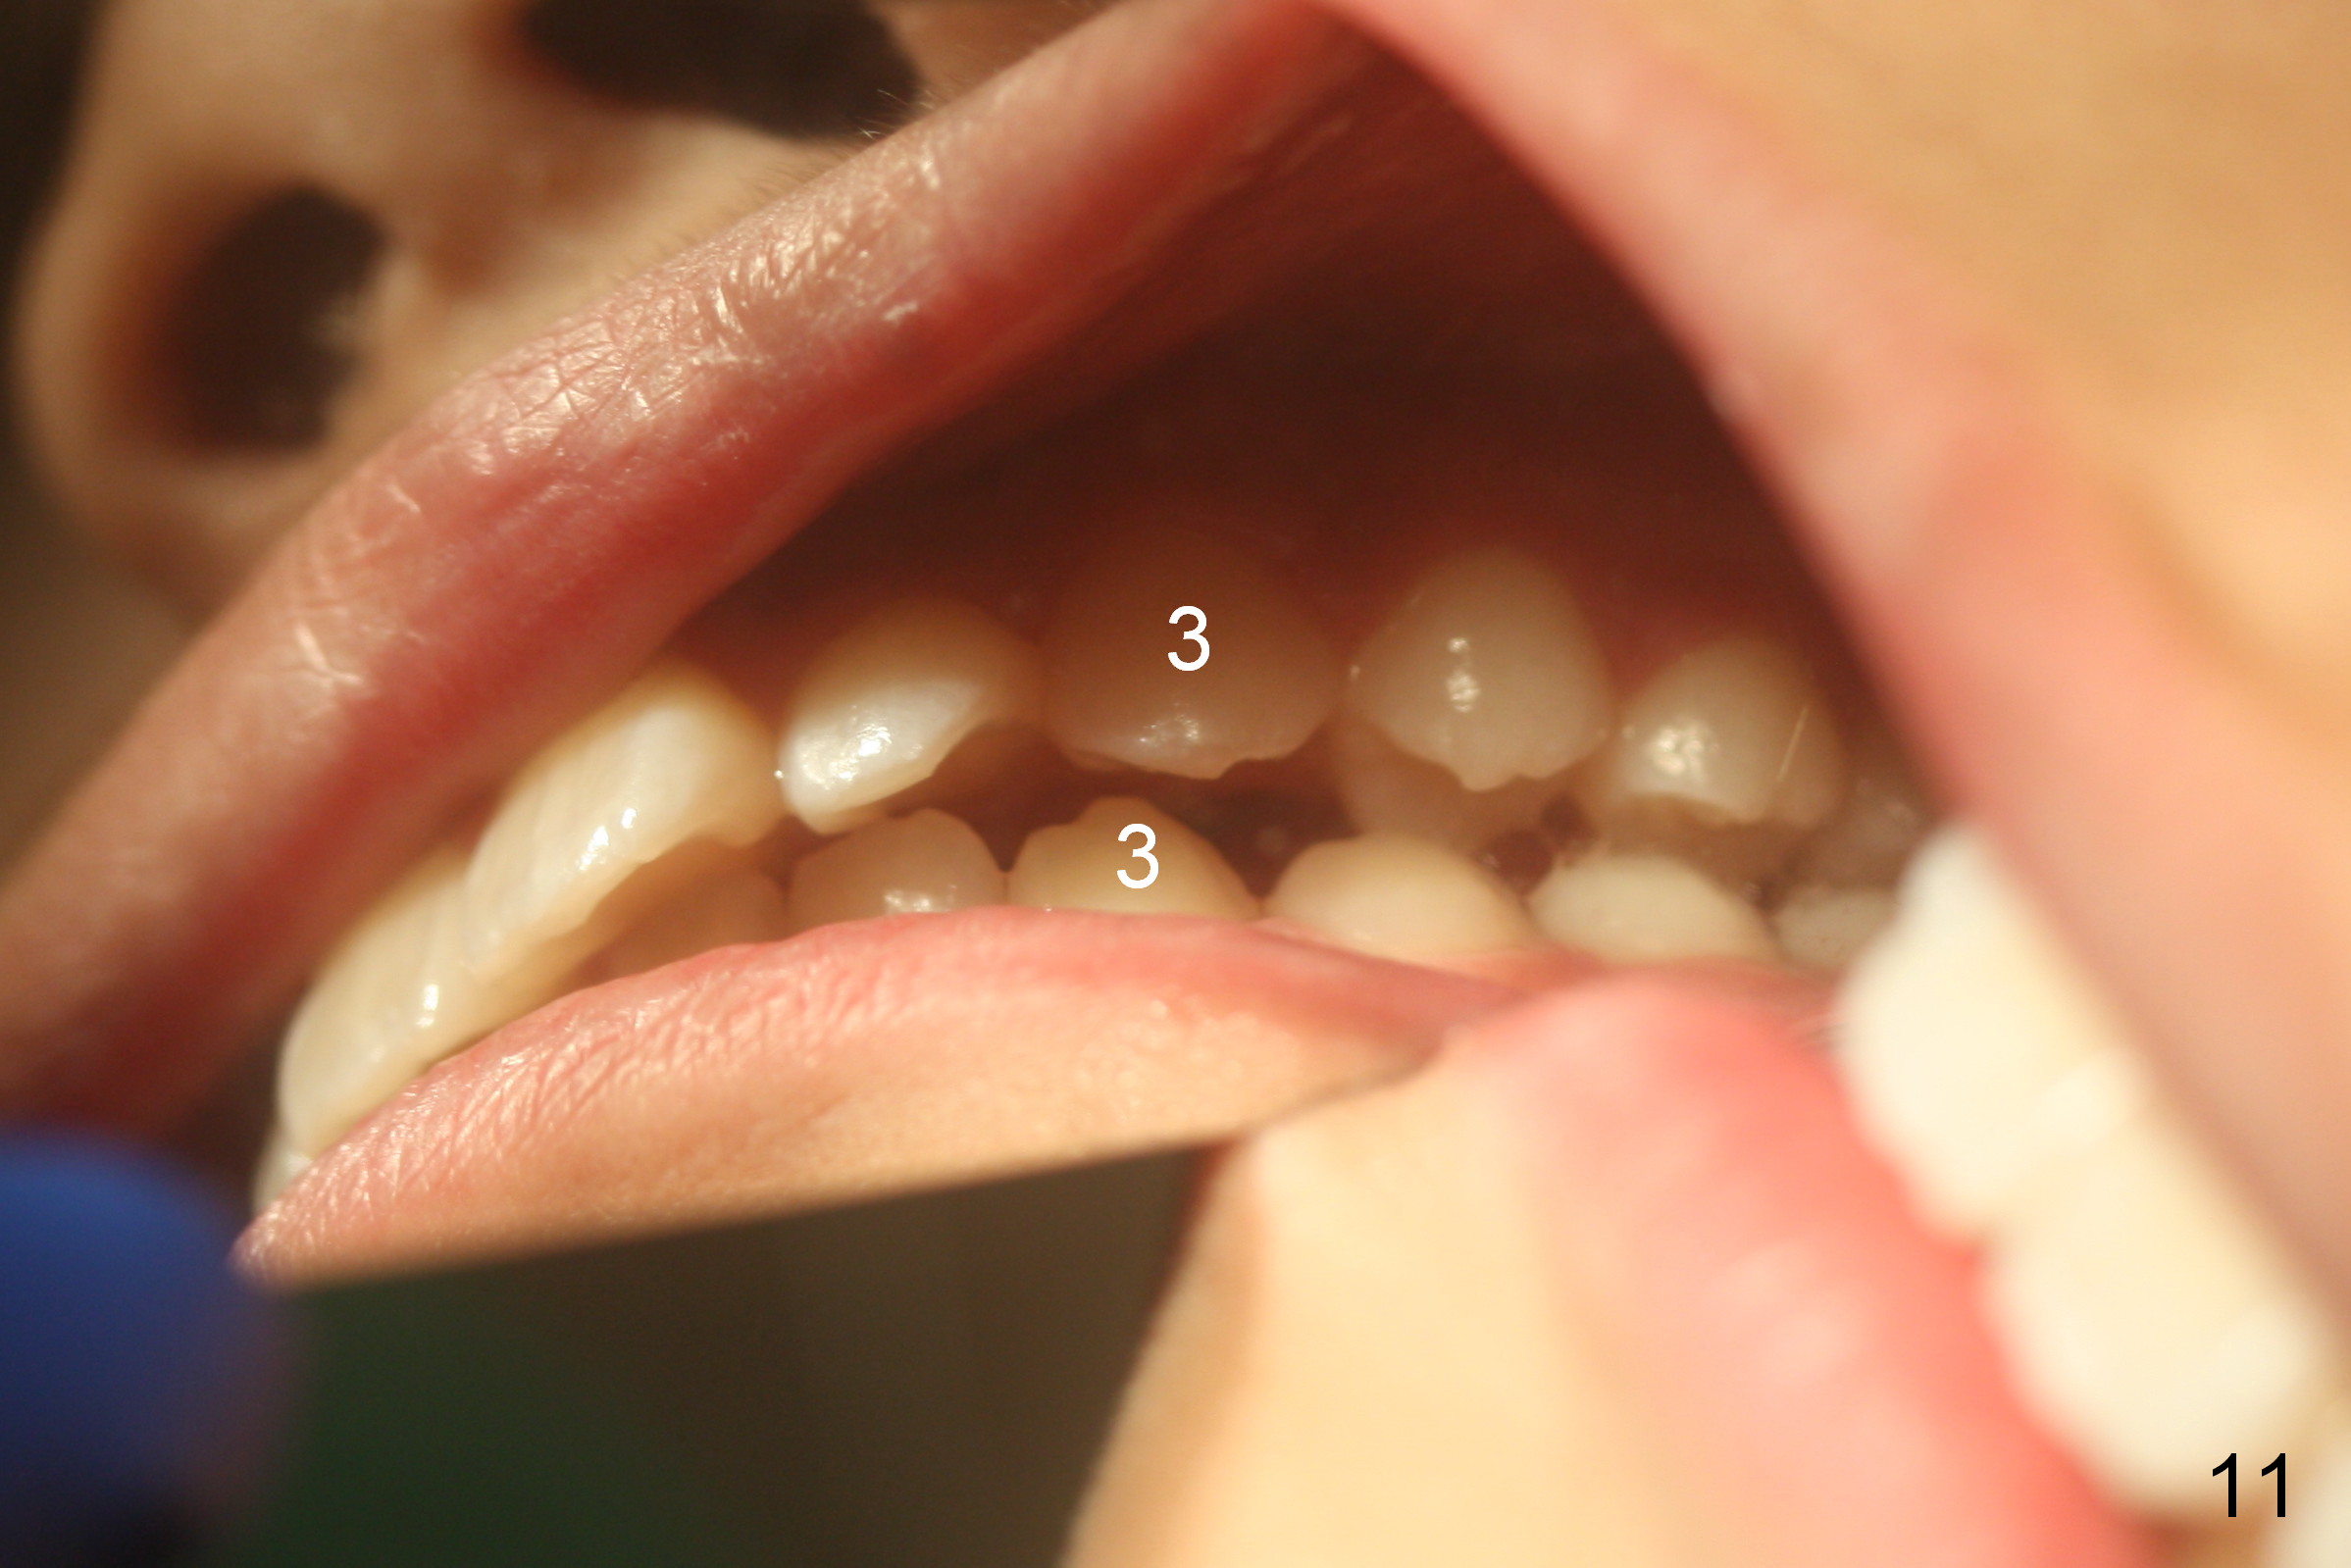

A 11-year-old boy has history of asthma. His father has sleep apnea with similar Class II malocclusion. Pan was taken for the boy 3 years ago (Fig.1). His mother wants to have orthodontic treatment as early as possible, because of protrusive upper anterior teeth. The dentition is permanent except the upper left canine and 1st molar (Fig.7,10,12,13 C, D). It appears that there is bilateral Class II occlusion at canine by half a tooth (Fig.9-12). The malocclusion and facial profile can be easily corrected with extraction of the upper 1st bicuspids.